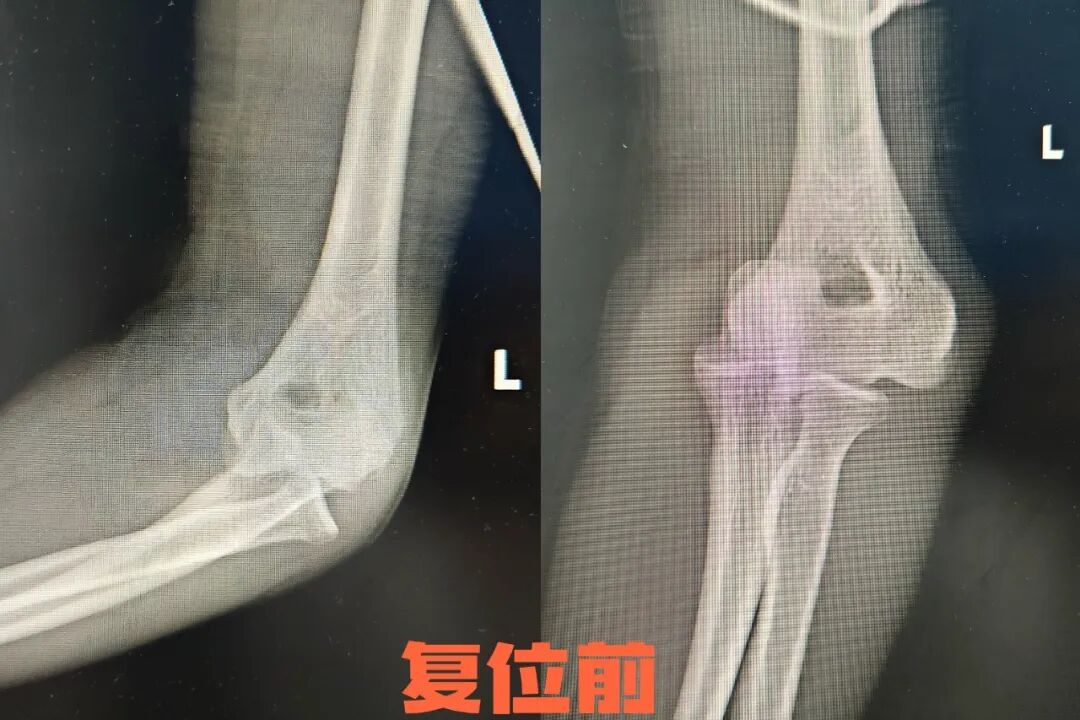

病例二

25岁的小张在篮球比赛中与队友碰撞后倒地,左肘呈屈曲位畸形,肿胀严重。小张立即来到长治二院急诊科治疗,急诊科团队迅速评估伤情,经X片检查确认患者为肘关节后脱位,立即实施牵引复位法。创伤骨科一病区杨志军医生与急诊科何龙医生双手分别握住患者上臂和前臂,进行手法牵引复位。复位后疼痛显著减轻,小张肘关节活动度恢复。随后用支具固定4周,配合康复锻炼,重返球场不是梦。